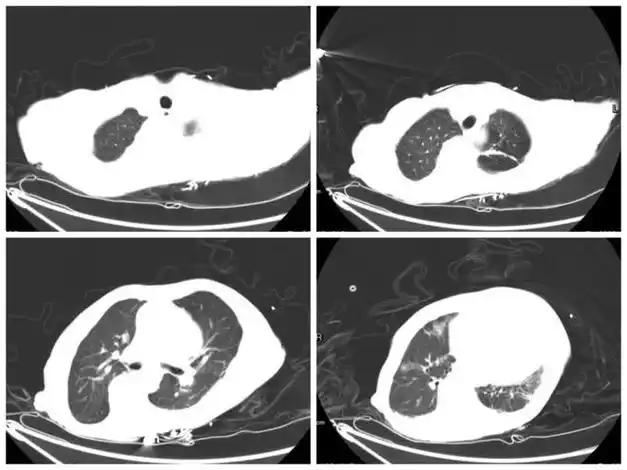

胸部ct:脊柱侧弯,左侧胸廓偏小,两肺微小结节,两肺散在炎性灶,左肺上

结核性胸膜炎后大面积漏斗胸合并扁平胸手术